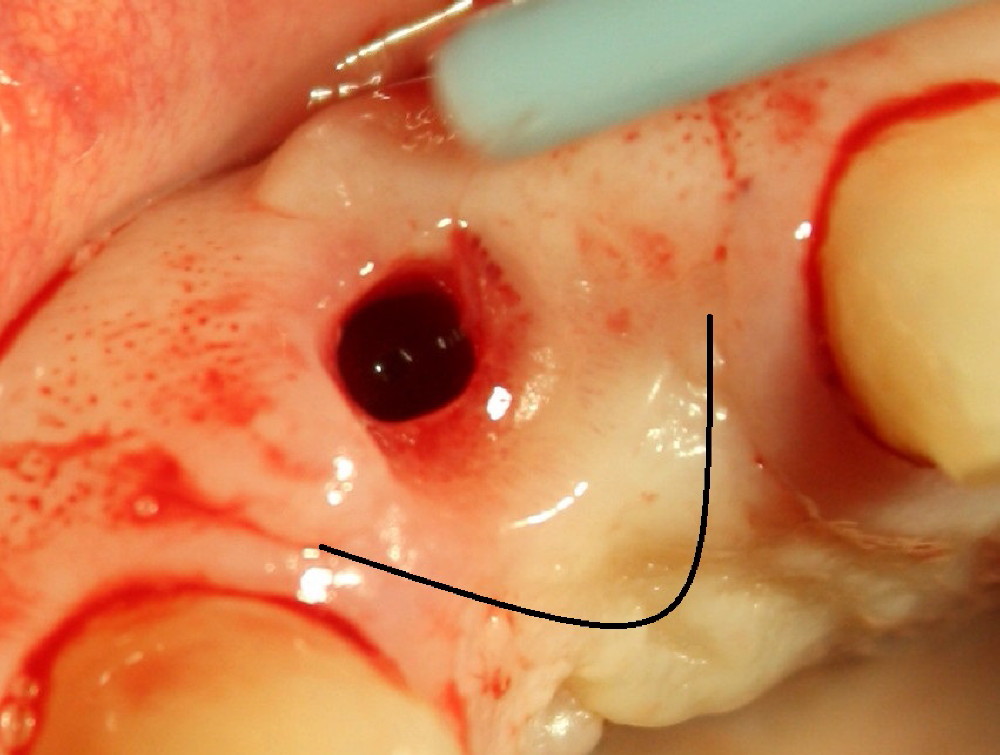

Malpositioned implant in the anterior region is cosmetically unacceptable. Immediate provisional allows us to note the issue immediately. The crown looks too long. Secondly, the provisional is easily dislodged, since the buccal aspect of the angled abutment is over trimmed (Fig.1). The implant (3.8x14 mm), which has been placed 3.5 months, is unexpectedly easily removed by reverse torque (Fig.2). The buccal wall is intact, whereas there seems to be enough bone lingually to place an implant. A small incision is made (Fig.11) so that the gingival tissue can be transferred buccally (Fig.12) and the immediate implant is to be placed palatally (Fig.13 white circle). There is no difficulty forming osteotomy in the palatal wall, followed by inserting 4.5x20 mm tap at the depth of 17 mm (Fig.3,5). But the tap is not palatal enough (Fig.4). By removing more palatal bone, the 4.5x17 implant (Fig.6) appears to be placed palatally enough for restoration (Fig.7; A: abutment; *: buccal gap). The biggest problem is that the palatal flap (Fig.7 arrowheads) cannot be pushed buccally; instead remains palatally. This leads to buccal tissue deficiency (Fig.8). Connective tissue graft is offered, but declined. The patient insists that she has low smile line. Following immediate provisional, mixture of allograft and synthetic graft is placed in the buccal gap (Fig.9). The overbuilt graft is held in place by perio dressing.

If a larger incision were made (Fig.14) and the flap were dissected freely (Fig.15), the buccal tissue deficiency would be less (Fig.16). Follow up is shown 2 3.